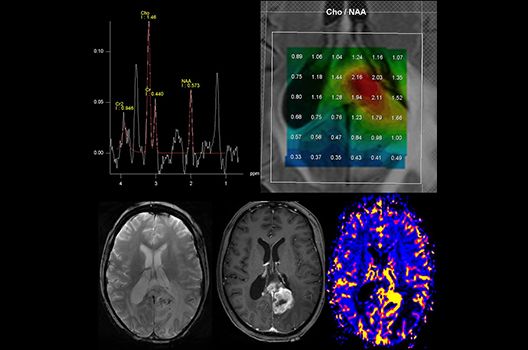

Die Schwerpunkte in der MR-Forschung liegen in der multiparametrischen und funktionellen Bildgebung bei onkologischen und anderen, neuroradiologischen Fragestellungen und umfassen die Anwendung modernster MR-Verfahren sowie die Untersuchung an Hochfeld-Geräten.

Die Magnetresonanztomographie (MRT) ist ein Verfahren, bei dem durch magnetische Kräfte Bilder des Körperinneren angefertigt werden. In der Neuroradiologie können manchmal kleinste Veränderungen schwere Folgen haben; daher forschen wir an der Entwicklung hochauflösender MRT-Sequenzen, mit denen diese Prozesse und auch einzelne Nervenfaserbahnen sichtbar gemacht werden können. Darüber hinaus sind bei vielen Erkrankungen des Gehirns die Blutgefäße betroffen. Daher arbeiten wir an der Neu- und Weiterentwicklung von MRT-Sequenzen zur Darstellung der Blutgefäße und zur Blutflussanalyse (sog. „Angio-MRT“). Einen besonderen Forschungsschwerpunkt unserer Klinik stellen die MR-Protonenspektroskopie und die funktionelle MRT dar, mit denen die Analyse einzelner chemischer Substanzen im Hirngewebe oder die Darstellung ausgewählter Hirnfunktionen möglich ist.

- PET/MRT in der Neuroonkologie

Die Hybridbildgebung mittels PET/MRT spielt insbesondere in der onkologischen Bildgebung eine wichtige Rolle. Eine mögliche Fragestellung ist die Unterscheidung zwischen einem Tumorrezidiv oder therapeutisch assoziierten Veränderungen insbesondere dann, wenn diese Frage mittels MRT alleine nicht beantwortet werden kann.

Die bildgebende Diagnostik und Verlaufsbeurteilung von Tumoren des Nervensystems ist einer der klinischen und Forschungsschwerpunkte unserer Abteilung. Eine besondere Bedeutung kommt der Hybrid-Bildgebung zu. Das Universitätsklinikum verfügt über einen integrierten Ganzkörper-PET/MRT-Scanner, der die Vorteile der MRT-Bildgebung und der Positronenemissionstherapie (PET) vereinigt. Aufgrund der langjährigen klinischen Arbeit und Forschungstätigkeit mit diesem Gerät hat die Neuroradiologie Tübingen maßgeblich zur Etablierung dieses Verfahrens beigetragen. Auch weiterhin forschen wir intensiv an neuen Methoden zur frühen Einordnung von Tumoren und insbesondere Tumorrezidiven, die mit anderen Methoden häufig nicht erfasst werden können.